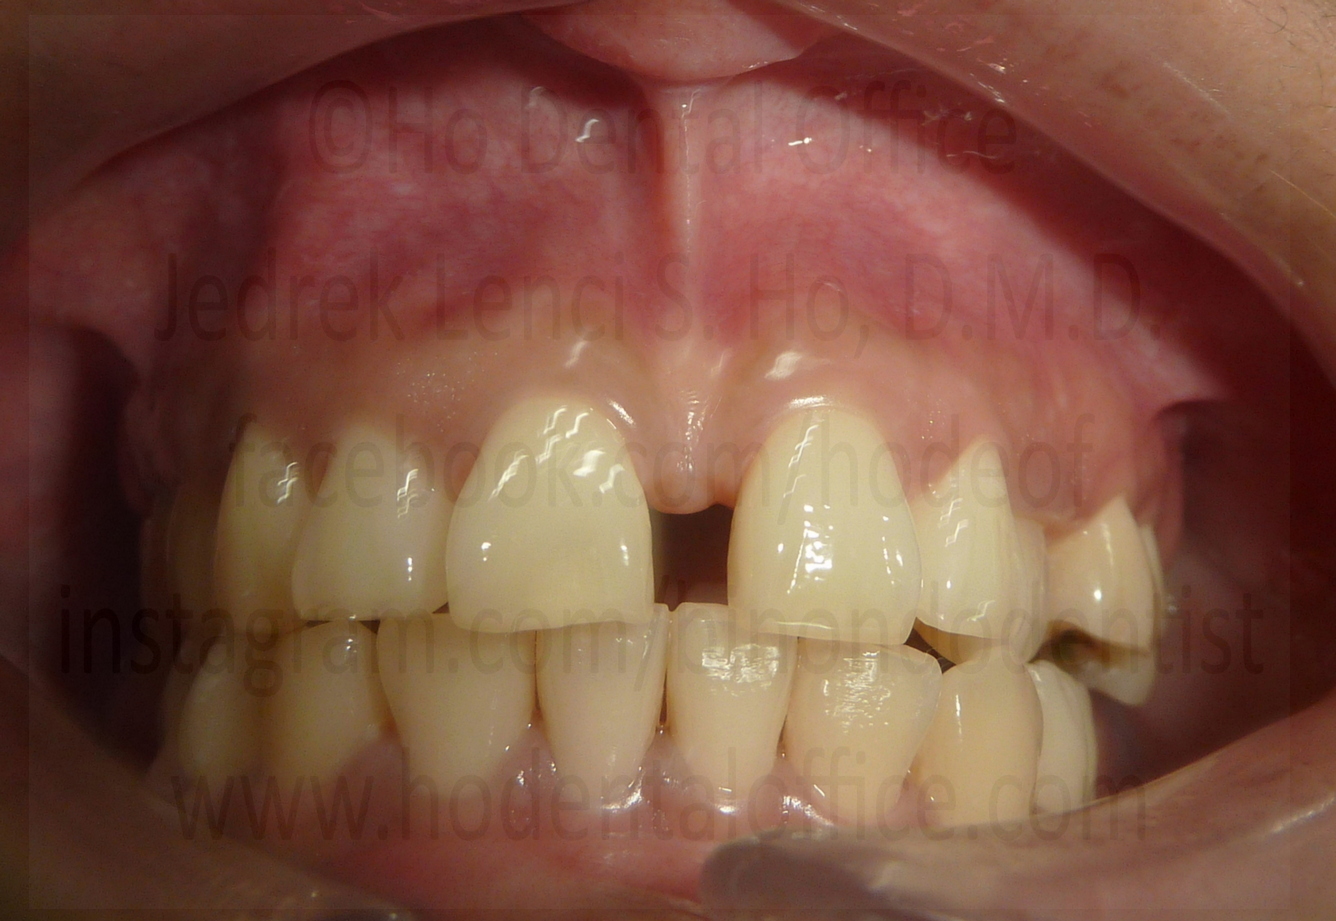

| examples of operculum located on lower third molars | |

Possible consequences of leaving an operculum intact includes, but not limited to:

- pericoronitis - inflammation of the gum specific to the area on top of the dental crown, maybe due to food debris becoming stuck and uncleanable

- dental cavities - due to food debris becoming stuck and uncleanable underneath the operculum

- traumatic contact - the operculum may be bitten by opposing tooth, causing injury